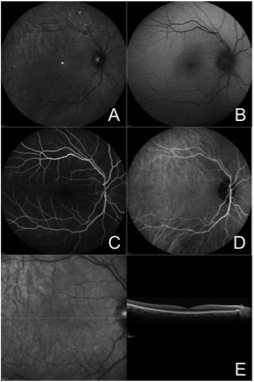

2 周后,左眼视力及眼底检查无明显变化(图 2)。FA 和 吲哚青绿血管造影(ICGA)仍显示微血管结构异常、渗漏及荧光遮蔽,ICGA 显示黄斑区脉络膜荧光异常(图 3)。SD-OCT 示视网膜内及视网膜下渗出,中心凹下少量网膜下液(图 4)。全身各项检查(血常规、C 反应蛋白、血沉、补体、自身抗体、感染指标等)均未见明显异常。

图 3 A 左眼 FA 示早(A)、中(B)、晚(C)期颞侧血管弓视网膜毛细血管渗漏,黄斑区及颞下血管弓荧光遮蔽;B 左眼 ICGA 示早(A)、中(B)、晚(C)期沿颞侧血管弓分布的微血管结构异常,黄斑区可见脉络膜改变

图 4 左眼 SD-OCT 水平(A)及垂直(B)径线扫描,可见黄斑区视网膜内及下方大量高反射渗出及 PED